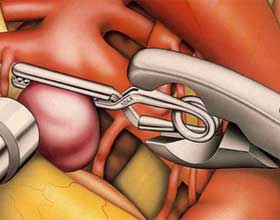

Когда речь заходит о клипировании аневризмы, подразумевается процедура, направленная на изоляцию аневризмы от общего кровообращения. Это достигается путем установки специальной клипсы на шейку пораженного сосуда.

В зависимости от типа аневризмы может понадобиться применение зажимов с обеих сторон. Для доступа к необходимой области выполняется трепанация черепа.

Во время проведения операции выполняются следующие шаги:

- Пациенту вводят общий наркоз.

- Производится трепанация необходимого участка черепа.

- С помощью кранитомы создается отверстие.

- Открывается твердая оболочка мозга.

- Выявляется пораженный участок и отделяется от окружающих тканей.

- Аневризма отключается от общего кровотока с помощью клипсы.

- Черепная коробка восстанавливается. Иссеченное отверстие фиксируется с помощью пластин и винтов.

Операция требует от хирурга высокой точности и внимательности. В процессе используются различные микрохирургические инструменты. Если врач замечает, что сосуды истончены, он может обернуть их хирургической марлей или фрагментами мышцы. Это поможет снизить риск разрыва при повышении давления.